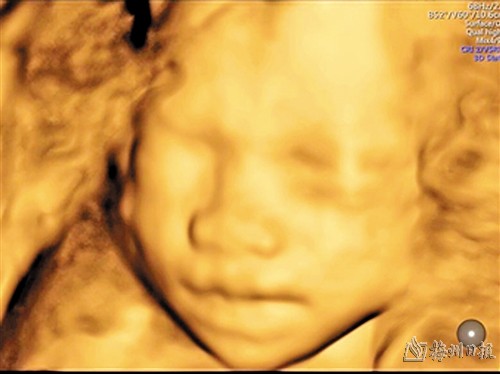

第三次超声检查图像

第三次超声检查:(20-24周+、系统四维+胎儿心脏筛查)

第三次超声检查,孕20-24周+进行系统四维超声检查,即III级筛查,此次筛查是整个孕期最主要及最重要的结构筛查,也称为大排畸。筛查包括胎儿颜面部(唇腭裂)、大脑、小脑、脑室系统、脊椎(脊椎裂、侧弯等)、骨骼(四肢、手掌、足底)、心脏、肾脏、肺、膀胱等发育不良。同时还有机会通过四维图像看到宝宝的样貌,可以有张嘴的样子、嘟嘴的样子或者微笑的样子。